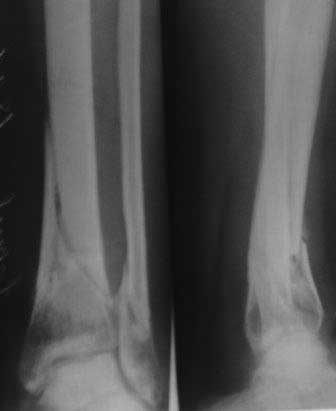

Пациентка 32 года, травму получила в результате ДТП, лечилась в гор.б-це №? Москвы с 19.07.по04.08.11г скелетным вытяжением, после наложена гипсовая повязка,(р-снимок 1,2.) после спадения отека гипс переведена в циркулярную, (видимо на другой вид лечения не хватило средств), гипс снят 19.11.11г(снимок-3) .Жалобы на боли при ходьбе через несколько шагов, увеличение отека в голени и г/стопном суставе, боли ноющего и неприятного характера, хромота, при осмотре отечность голени в с-н/з и г/с суставе, при пальпации умеренная болезненность в н/з голени, подошвенное сгибание в г/с суставе ограничена и болезненна. Работа связана с ходьбой, просить помочь чтобы не потерять работу. Пока в голове только КДО аппаратом Илизарова, уважаемые коллеги помогите советом! Доступно БИОС, пластины DCP. и прилагается последние р-снимки.